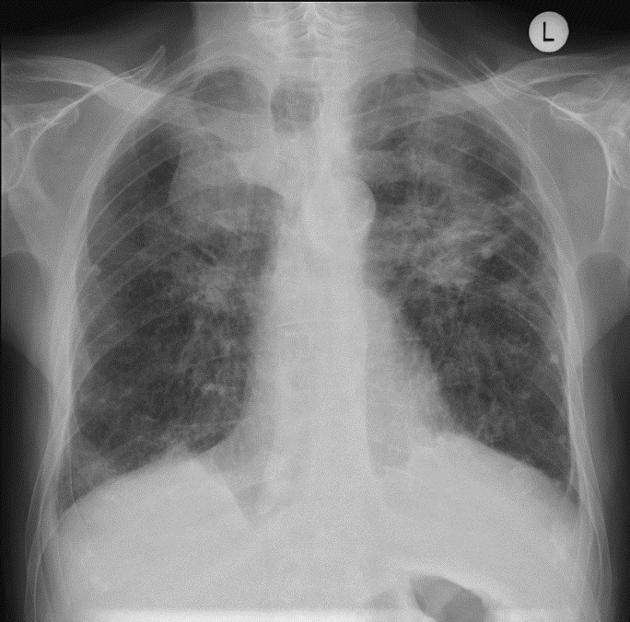

Обследование проводится в прямой и боковой проекциях грудной клетки, с прицельной съёмкой подозрительных участков, а при необходимости — в косых проекциях, в режиме обзорной рентгенографии для выявления прямых признаков пневмокониоза. Цель обследования — выявление рентгенологических сигналов интерстициальных и узелковых изменений, оценка степени распространённости фиброзных изменений, а также состояния корней лёгких и плевры.

Рентгенография выявляет следующие признаки пневмокониоза:

Диссеминированные узелковые тени диаметром 1–10 мм с преимущественной локализацией в верхних и средних отделах лёгких, сигнализирующие о пылевых отложениях и фиброзе.

Сетчато-ячеистый рисунок лёгочной ткани, отражающий интерстициальное уплотнение и сращение межальвеолярных перегородок.

Уплотнение и расширение корней лёгких, свидетельствующее о вовлечении перибронхиальных и периваскулярных тканей.

Утолщение плевры с возможными кальцинатами, особенно по верхушкам и междолевым щелям, что указывает на плеврофиброз.

При прогрессирующем течении — крупные конгломераты из сливающихся узелков и деформация лёгочного рисунка с признаками «сотового лёгкого».